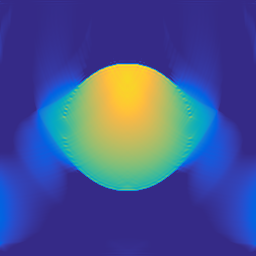

A 2D scenario: Ω=[0,1]2Ωsuperscript012\Omega=[0,1]^{2} with inhomogeneous medium properties and an irregular sensor geometry, see Figure 1. The medium properties vary in the range encountered, e.g., in the human breast [19].

Figure 1: 2D PAT scenario (II) used in the numerical studies. The spatial resolution is N=5122𝑁superscript5122N=512^{2} plus 242424 pixels of PML layer in all directions. LABEL:sub@subfig:2DScenarioA The scenario cosists of three materials: Material A (covering the top part of the domain): c=1500𝑐1500c=1500, ρ0=1000subscript𝜌01000\rho_{0}=1000, material B (parabolic-like part): c=1400𝑐1400c=1400, ρ0=1200subscript𝜌01200\rho_{0}=1200, material C (vessel-like part): c=1560𝑐1560c=1560, ρ0=800subscript𝜌0800\rho_{0}=800. LABEL:sub@subfig:2DScenarioB Ground truth p0subscript𝑝0p_{0} and sensor configuration (white pixels, 200200200 sensors at the interface between materials A and B.)